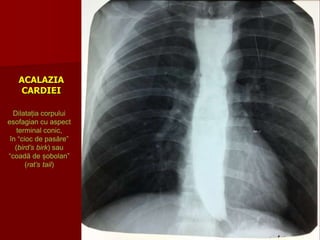

ACALAZIA CARDIEI

Dilatația esofagului cu aspect terminal conic în formă de “cioc de pasăre” (bird’s birk)

sau “coadă de șobolan” (rat’s tail)

ACALAZIA

CARDIEI

Dilatația corpului

esofagian cu aspect

terminal conic,

în “cioc de pasăre”

(bird’s birk) sau

“coadă de șobolan”

(rat’s tail)

ACALAZIA CARDIEI:

• stare de permanentă contracţie a cardiei

• cardia apare mult îngustată cu contururi

bine delimitate, netede, cu pliuri paralele,

centrează segmentul supraiacent

• esofagul toracic este dilatat în grade

variabile uneori foarte mult

• esofagul se alungeşte şi se cudează

• undele peristaltice sunt frecvente,

profunde, dar ineficiente

• evacuarea este lentă în cantitate mică

• staza esofagului constituie un factor

favorizant al esofagitei.

• Pentru acalazia cardiei veriga principală a patogeniei este lipsa

reflexului de deschidere a cardiei în momentul deglutiţiei şi diminuarea

funcţiei motorice de propulsare a esofagului.